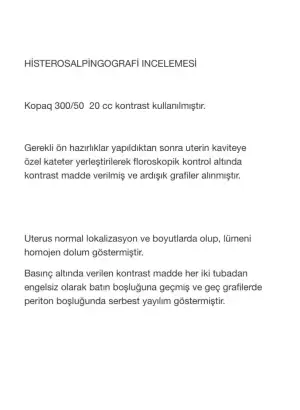

Hanımlar merhaba, mart ayında tedavisiz hamile kaldım ve düşük yaptım. Sonrasında tedavi için hastaneye gittim doktorum Hsg çekti ve sağ tüpümde enfeksiyondan dolayı tıkanma olduğunu ve ameliyat olmam gerektiğini söyledi. Eğer ameliyat olmazsam hamile kalmam zorlaşacak kalsamda enfeksiyon bebeğe zarar verecek dedi. Sonrasında hemen ameliyata karar vermek istemediğim için gitmediğim doktor kalmadı neredeyse ve diğer doktorların hepsi ameliyatlık bir durum olmadığını söylüyor hsg raporunu onaylayan radyoloji doktoru da dahil. Hsg yi çeken kadın doğum doktoru ise hala olmam gerektiğini idda ediyor. Psikolojim çok bozuldu hsg görüntülerimi bırakıyorum buraya bu durumu yaşayan varsa lütfen yardımcı olabilir mi? Ameliyat olmayıp bir daha düşük yaparsam diye çok korkuyorum.